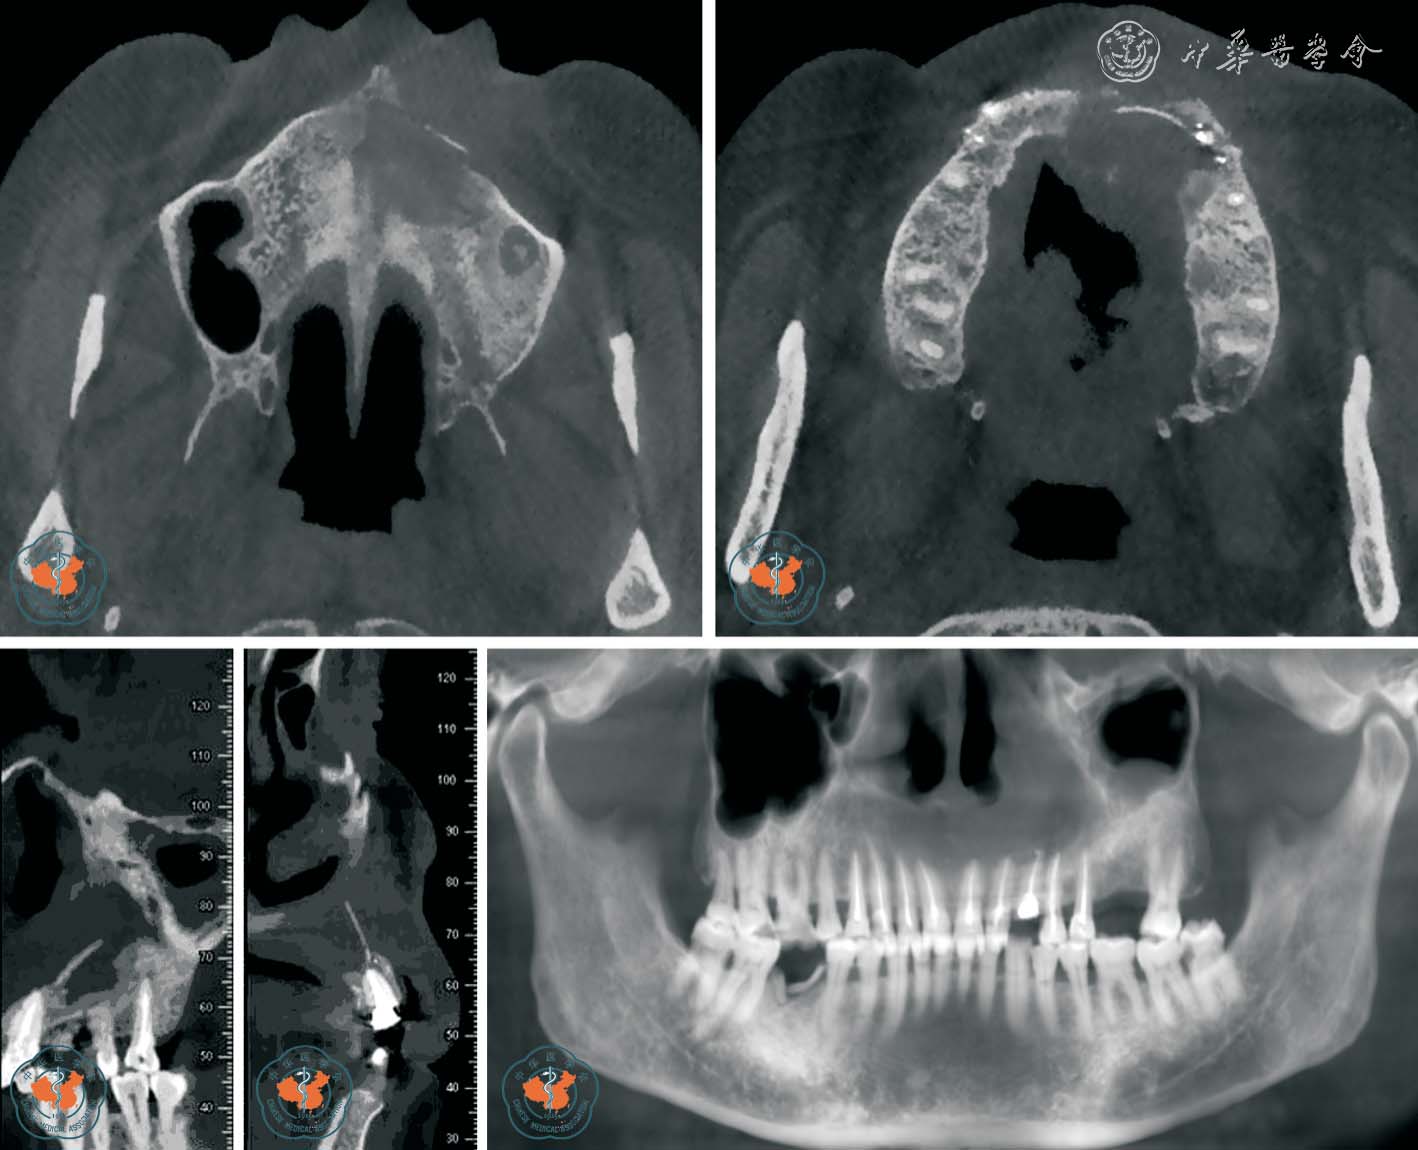

5. 诊断根管侧壁穿孔:Young16报道,对普通根尖片不能诊断根管侧壁穿孔的病例用CBCT 进行分析,发现CBCT 图像显示根管侧壁穿孔明显,有助于早诊断、早治疗,提高治疗效果。 Lofthag-Hansen 等17也指出,CBCT 较根尖片对根管侧壁穿孔的诊断率较高。 另外,传统牙片显示根管充填良好,未见侧壁穿孔,牙胶尖定位显示窦道来源于牙根侧方,通过CBCT 影像分析,发现根管侧壁穿孔位置,行穿孔修补术后,疗效良好(图7)。

图7 CBCT 轴位、MPR 及VR 重建上颌中切牙清晰显示根管侧壁穿孔

6. 牙髓病治疗失败原因的评价:根管充填不严密、超充、遗漏根管、器械断入是牙体牙髓疾病治疗失败的主要原因。 而普通口内X 线摄片常因采用不同角度投照,胶片、牙齿、X 线球管三点不能垂直在一条直线上,往往使图像相互重叠,不能清晰显示牙根走向、细小根管弯曲程度,对临床医生有误导作用,致使根管治疗后仍有反复肿胀等症状。 通过对根管治疗后仍有症状的牙体牙髓病患者行CBCT 检查,运用三维成像技术对患牙进行多层面分析,均明确病因,提高了根管治疗的成功率18,见图8 ~9。

图8 CBCT 轴位、CPR 及MIP 重建显示左侧中切牙后方舌侧骨板因左上尖牙超充引起继发感染

图9 CBCT 轴位及MIP 重建显示右上颌6 近中根管有高密度异物(断针位于右上颌6 近中根管内)